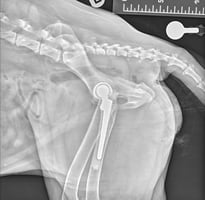

Larger diameter bone screws are usually placed, in an attempt to limit the risk of fatigue failure of the screw (Figure 3). Use of a shaft screw with a large unthreaded portion and a negative profile thread engaging in the trans-cortex has also been reported, as these screws also offer increased resistance to fatigue failure. However, healing of the fissure has again been reported to be inconsistent.

Recently, a HIF-specific implant has been marketed. It is a titanium screw which is self-compressing, with a bone void around the central non-threaded mid-portion, which is filled at surgery with demineralised bone matrix. Outcomes after placement of this screw are unknown at this time.